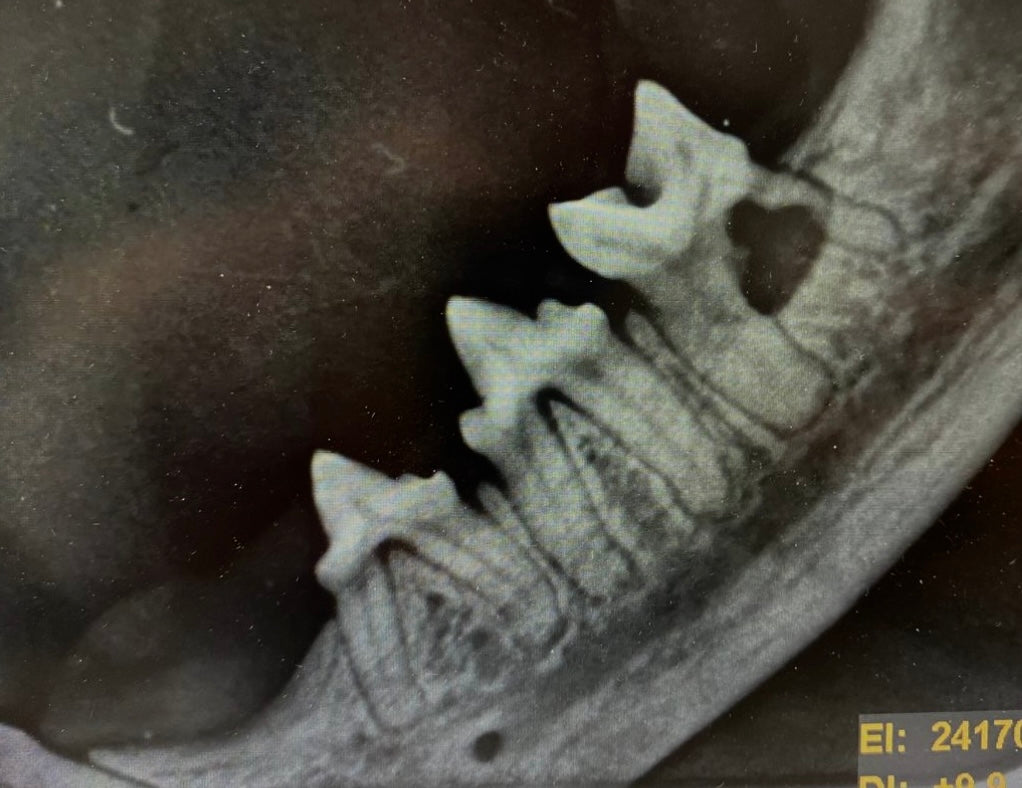

Wir freuen uns, nun auch dentale Röntgenbilder anfertigen zu können!

Damit können wir die Diagnostik und Behandlung von Zahnerkrankungen noch genauer durchführen und individuell anpassen.